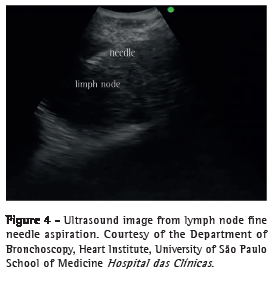

Wang needle (21G) transtracheal/transbronchial aspiration is still often used in conventional bronchoscopy because of its ease of use, safety, and low cost; however, up to 43% of the collected samples are unsatisfactory for diagnosis.(18) Available in Brazil, EBUS needles measure 22G in diameter, are provided with a protective sheath, have an exposure of approximately 4 cm, and have two to three safety locks to reduce the risk of accidents related to aspiration (vessels and other mediastinal structures) and the risk of perforation of the working channel of the device. The needle set includes a dedicated valve that fits into the working channel port of the device, thereby making it possible to connect the needle to the EBUS equipment. Once the needle is introduced into the working channel, it should be pushed until it fully fits into the valve connected to the device and is locked. The sheath should remain exposed until it is seen bronchoscopically, and only then can the safety lock of the needle be released. The needle should be advanced through the tracheobronchial wall in order to aspirate paratracheal or peribronchial lymph nodes or lesions (Figure 4).

The device should be passed through the larynx with caution, given that the bronchoscopic view is oblique and the ultrasound probe is located posteriorly to that view. Subsequently, ultrasound imaging of the lesion that will be diagnosed or of the first lymph node station that will be aspirated should be performed. After the tip of the device touches the tracheobronchial wall, the balloon should be inflated with distilled water so that the ultrasound probe is flat against the tracheal or bronchial wall, and the best ultrasound window to the lesion or lymph node should be found before aspiration. A 3- or 4-cm ultrasound depth is sufficient for the purpose of the examination. At this point, the gain, contrast, and brightness of the ultrasound image can be adjusted to obtain the highest resolution image of the lesion or structure. Doppler is recommended to differentiate between solid structures (lymph node or tumor) and vascular structures (Figure 3).(6)